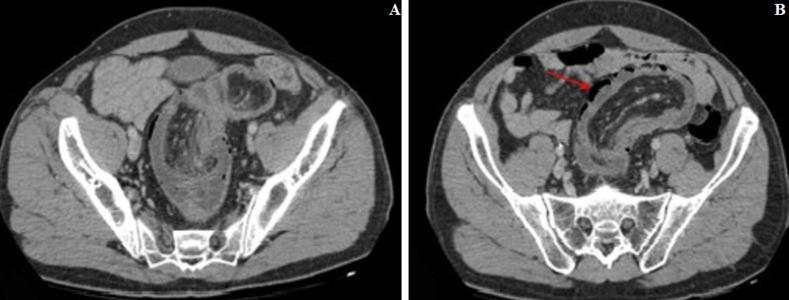

Colo-rectal intussusception is rare in adults and is often secondary to malignant lesions, rarely benign lesions such as colonic lipomas can also be the cause. We present the case a 60-year-old man who presented to the emergency department with acute abdominal pain. On physical examination, the abdomen was distended with diffuse tenderness. CT scan of the abdomen revealed a colo-rectal intussusception secondary to a rectal lipoma with parietal pneumatosis of the invaginated loop. An emergency laparotomy was performed. Intraoperatively the radiological findings were confirmed. A rectosigmoid resection (Hartmann's procedure) taking off the lipoma and the invaginated segment of the colon was performed and the patient had an unevent full recovery. Histopathology confirmed a 6cm sub-mucosal lipoma without evidence of malignancy. As the diagnosis of a benign disease in patients presenting with colonic intussusception can only be made on pathological examination, this entity should be managed as a malignant lesion due to the high incidence of malignancy.

直肠-结肠肠套叠在成人中较为罕见,常继发于恶性病变,良性病变如结肠脂肪瘤也很少见,但也可能是病因。我们报告 1 例 60 岁男性,因急性腹痛就诊于急诊科。体格检查发现腹部膨隆,全腹压痛。腹部 CT 扫描显示直肠脂肪瘤继发的直肠-结肠肠套叠,套叠肠襻壁积气。行急诊剖腹探查术。术中证实了影像学发现。行直肠乙状结肠切除(Hartmann 手术),切除脂肪瘤和套叠的结肠段,患者恢复顺利。组织病理学证实为 6cm 黏膜下脂肪瘤,无恶性证据。由于仅通过病理检查才能诊断出患有结肠肠套叠的患者为良性疾病,因此鉴于恶性病变的高发生率,应将此类疾病视为恶性病变进行处理。